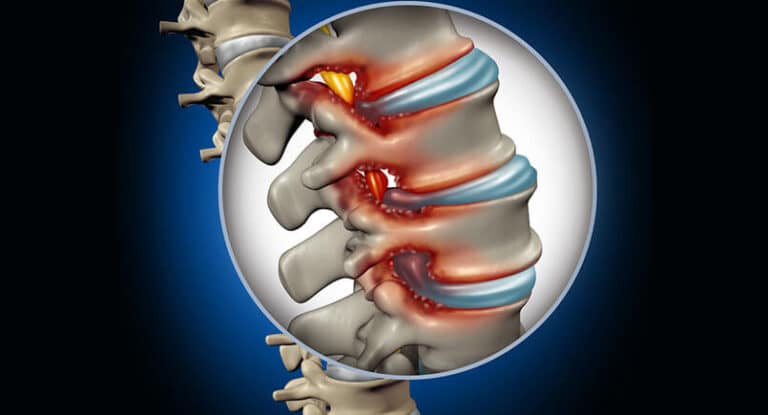

عملية الغضروف: عملية الانزلاق الغضروفي بالمنظار وكم مدة التعافي بعدها؟

عملية الانزلاق الغضروفي بالمنظار، الانزلاق الغضروفي يعتبر أحد أمراض العظام والذي يصيب الغضروف ما بين الفقرات تحديدا ويؤثر…

ما هي أنواع مرض الغضروف؟

اعرف أكثر عن أعراض الغضروف

أليك أهم اعراض غضروف القطنية